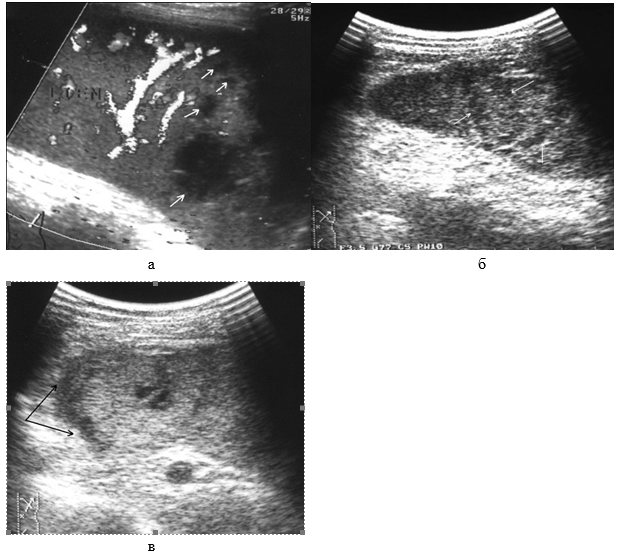

Прямым и наиболее постоянным (в течение острого периода травмы) эхографическим признаком подкапсульных разрывов селезенки с образованием внутриорганных гематом является наличие в паренхиме эхонегативной зоны (рис. 2, а, б). При гематомах, локализовавшихся в области полюсов селезенки или по ее диафрагмальной поверхности, эхонегативная зона имеет серповидную форму, повторявшую контур органа (рис. 2, в).

Рис. 2. Эхограмма подкапсульного разрыва селезенки: а – внутриорганная гематома; б – линейные разрывы паренхимы; в – подкапсульная гематома.

Необходимо указать, что при первичном исследовании (3–5 часов после травмы) ни в одном наблюдении не представилось возможности достоверно выявить подкапсульный разрыв селезенки в виде эхонегативной зоны. Повреждения визуализировались как нечетко очерченные участки паренхимы с незначительно сниженной эхогенностью, имевшие «смазанную» структуру, нехарактерную для паренхимы селезенки (рис 3).

Рис. 3. Эхограмма подкапсульного разрыва селезенки (3–5 часов после травмы). Зона повреждения указана стрелками.

Сканирование селезенки через 8–12 часов после травмы позволяет выявить прогрессирующее неравномерное снижение акустической плотности в зоне интереса (рис. 4, а). Устойчивая визуализация эхонегативной зоны (внутритканевой гематомы) становится возможной по истечении первых суток посттравматического периода (рис. 4, б).

Рис. 4. Эхограмма подкапсульного разрыва селезенки: а – через 8–12 часов после травмы; б – через 1 сутки после травмы.